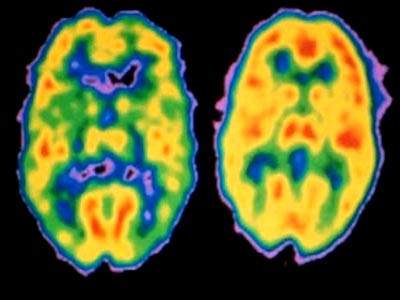

Não người bị tâm thần phân liệt (trái) và não lành mạnh. |